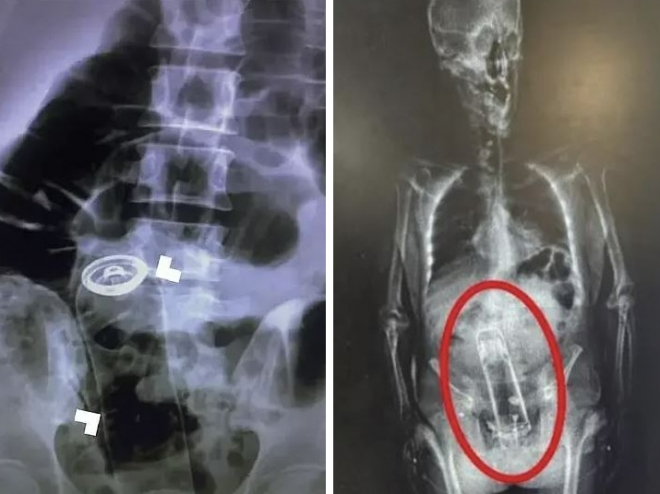

2023년 응급외과학술지에는 이란 남성이 항문에 삽입한 데오드란트가 소화관을 타고 올라가 응급 수술을 받은 사례가 실렸다.

지난해 미국 플로리다에서는 마약 소지 혐의로 체포된 남성의 체내에서 보온병이 발견되기도 했다.

미국 응급의학저널에 따르면 2012년부터 2021년까지 매년 평균 3만 8948명이 직장 이물질로 입원했다.평균 환자 나이는 43세였고,78%가 남성이었다.40%는 입원 치료가 필요했다.

의사들이 꺼낸 물건 중 55.4%는 성인용품이었다..